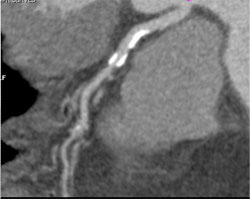

Diseased LAD